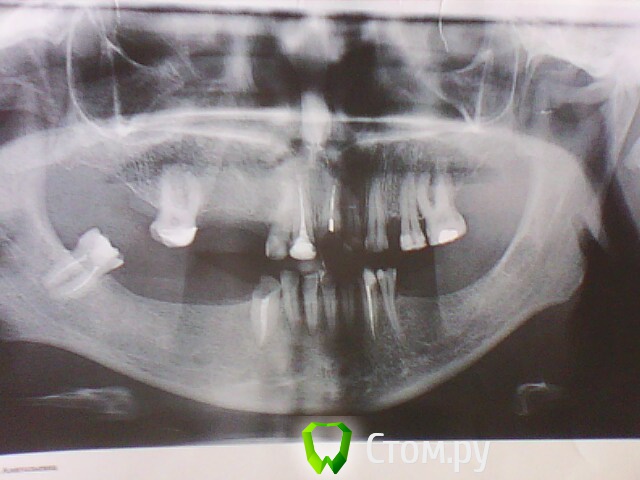

ОльгаS Опубликовано 4 октября, 2014 Поделиться Опубликовано 4 октября, 2014 Здравствуйте. Вот при таком варианте: Ссылка на комментарий

anvladd Опубликовано 4 октября, 2014 Поделиться Опубликовано 4 октября, 2014 Съемное, импланты. 3 Ссылка на комментарий